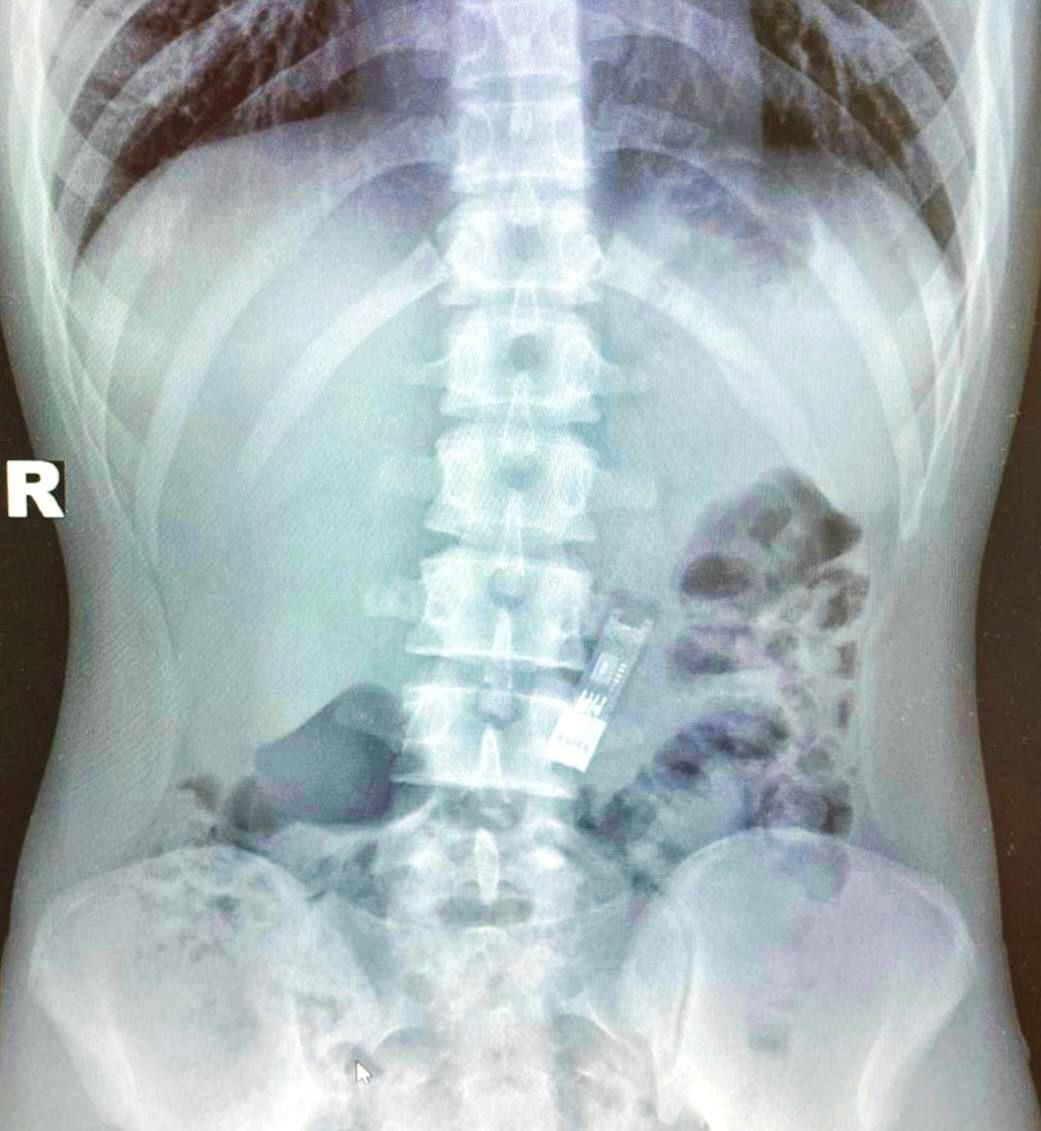

Как рассказал сам 16-летний парень, он сделал домашку, загрузил её на носитель, а потом стал дурачиться. Настолько, что случайно проглотил флешку. Сначала надеялся, что всё выйдет само. Но не вышло. Поэтому пришлось ехать в больницу.

Врачи сделали рентген, обнаружили 32 гб в желудке и достали их с помощью специальных щипцов. Без единого разреза. Медики справились всего за 15 минут и уже на следующий день выписали мальчика. Домашку он в итоге сдал.